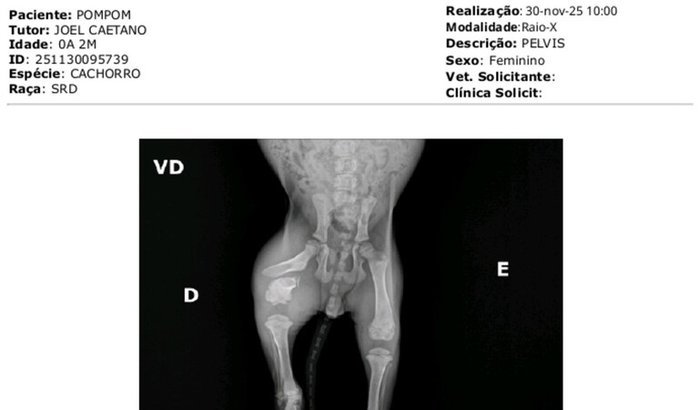

Olá, eu sou a Cristiane Caetano dos Santos. Recentemente, meu irmão encontrou uma cachorrinha chamada PomPom que foi atropelada e precisa urgentemente de uma cirurgia para tratar seus ferimentos. Nós a levamos para avaliação, mas o custo do procedimento ultrapassa nossas possibilidades no momento.

Enquanto meu irmão cuida dela com todo carinho em casa, PomPom ainda sente muita dor e precisa de cuidados médicos especializados. Estamos em busca de um veterinário que aceite nos apoiar com valores mais acessíveis ou parcelados, e qualquer indicação será de grande ajuda.